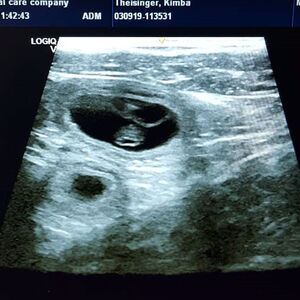

Am 10.08.2019 belegte Barolo die Hündin Avalon vom Felsengarten (Rufname Kimba).

Die beiden waren sich sofort sympathisch, aber erst als die „große Schwester“, die in Begleitung dabei war, im Camper verblieb, hat sich Barolo getraut.

So hat Kimba vom 10. auf den 11.10.2019 ihren A-Wurf mit 11 Welpen (7 R | 4 H) zur Welt gebracht.